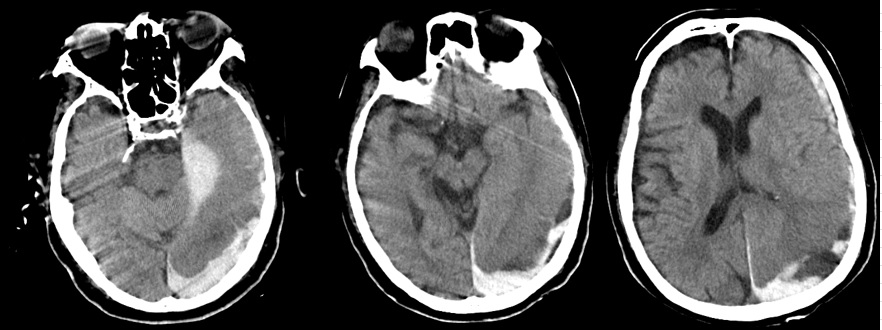

- 9月12日:急性硬膜下血腫

死亡した日の頭部CTで重度の急性硬膜下血腫。医師によれば「その原因はDICによる出血傾向」(頭部打撲の説明なし)。

証拠:頭部CT・急性硬膜下血腫

- 9月12日:出血傾向はごく軽度

PT-INR 1.3, APTT 35 sec, 血小板3.6万/μl, Hb 8.2 g/dl:出血傾向はごく軽度で硬膜下血腫の自然発生は否定的。この時、父は意識がなく自ら動くことはできない状態であったため、頭部を殴打された可能性しか残らない。

この時、撮影された頭部CTで急性硬膜下血腫が認められた。これが父の直接の死因となった。 医師からもその説明があったが、 直接の原因と推定される「頭部打撲」には一切言及がなく(録音記録あり)、 DIC(播種性血管内凝固)に伴う出血傾向による自然出血とのことだった。 しかしほぼ同時に行われた血液検査では、「PT-INR 1.3, APTT 35 sec, 血小板3.6万/μl」と 出血傾向はごく軽度であり、自然発生的に頭蓋内に出血を起こす可能性は皆無と言ってよい。

このことから、直接の死因である急性硬膜下血腫の原因は頭部打撲と確定できる。 この時点で父の意識はなく、自ら動くことは全くできない状態であることから、 頭部打撲は外力によって起こった、と推定される。つまり変死である。

硬膜下血腫がなかったとしても父は回復不能であり、早晩、死に至る病状ではあった。 医療事故を闇に葬るための故意の放置、そして死期を早めるための頭部殴打、 というのが、医療記録と経過から必然的に導き出された結論である。